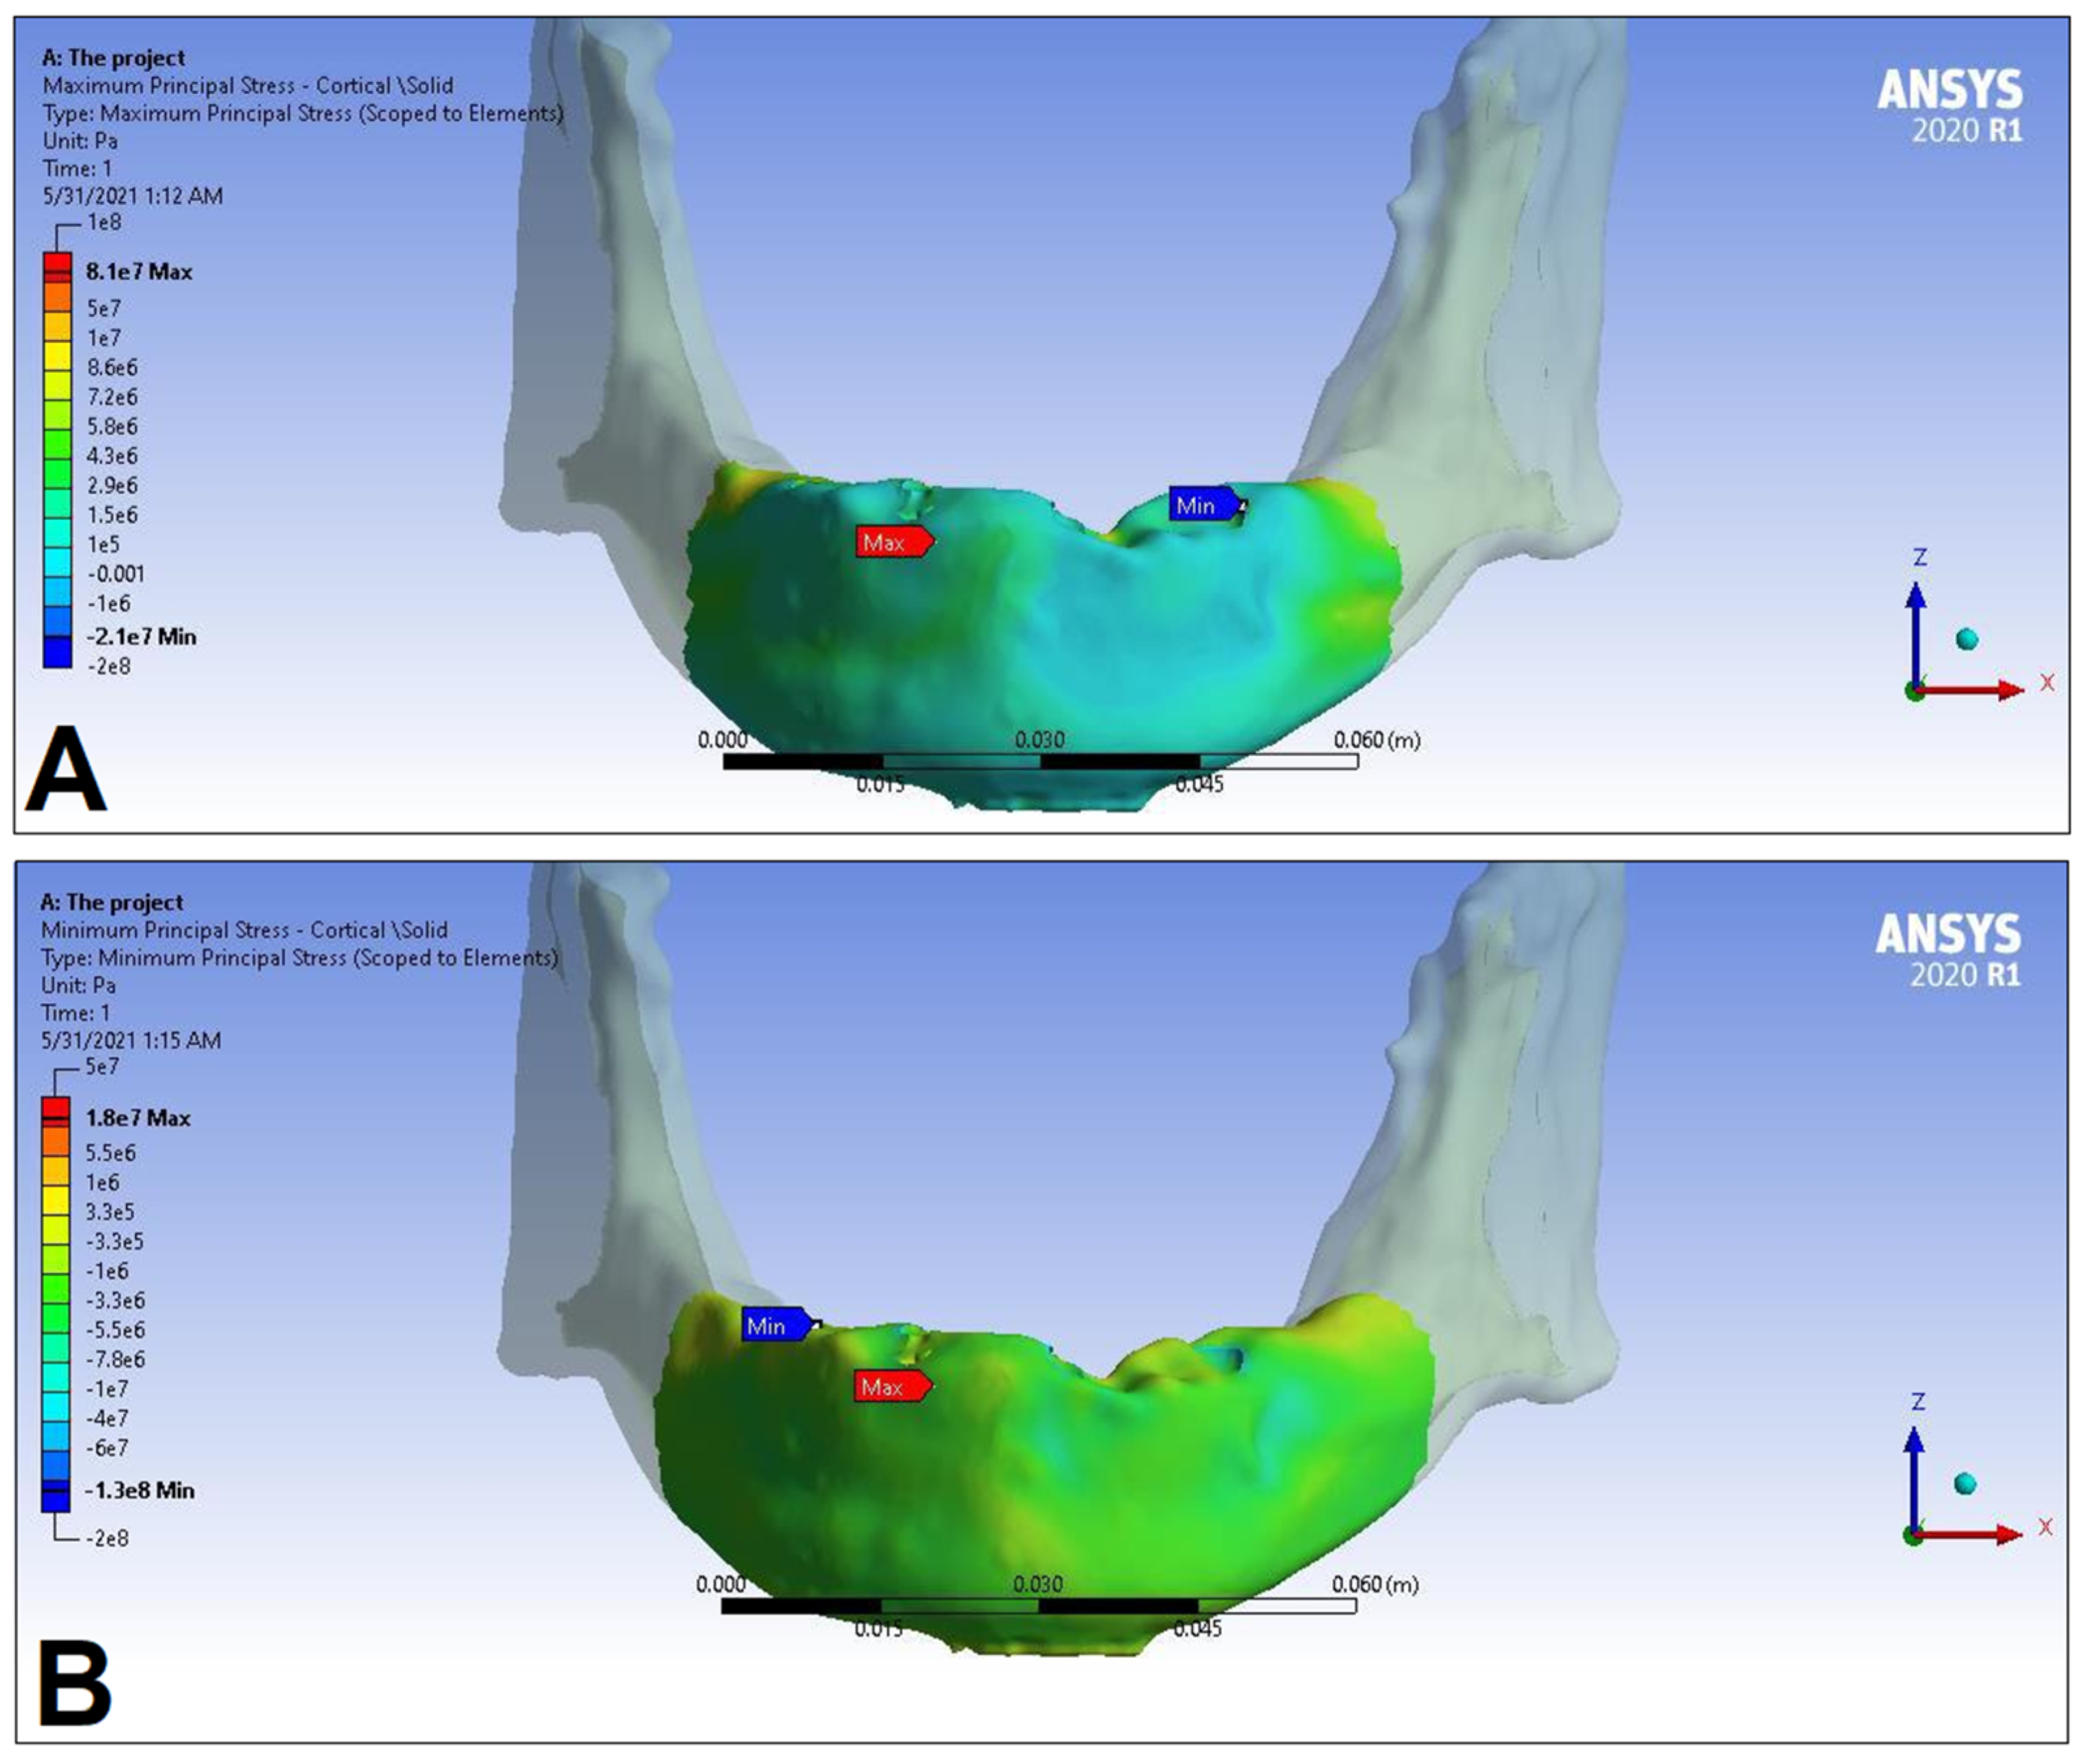

3. Results

| Cortical bone | Pmax [MPa] | 76.39 | 88.51 | 89.57 | 102.98 | 85.63 | 95.48 | 81.02 | 93.15 |

| Pmin [MPa] | −115.30 | −222.76 | −136.4 | −265.35 | −172.30 | −252.61 | −125.20 | −235.32 | |